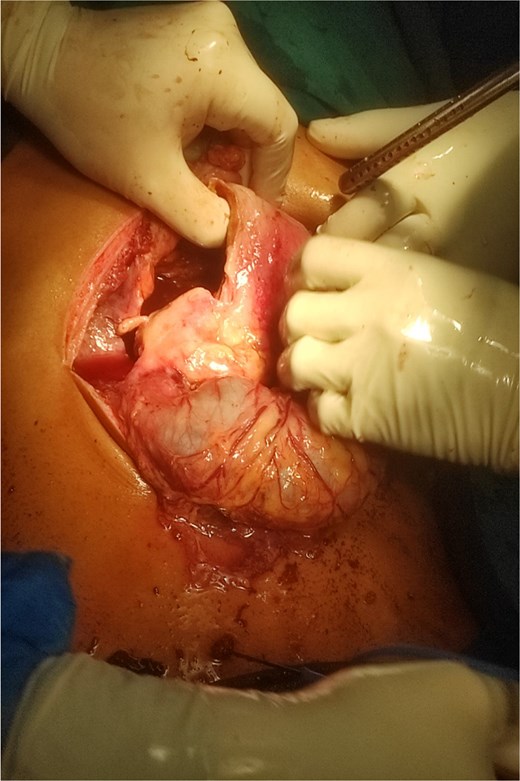

Patient was a fluid non-responder and was kept on ionotropic support of noradrenaline at 0.33 micrograms/kg/min in the emergency room. Given the clinical presentation and hemodynamic instability we decided to plan for exploratory laparotomy and damage control surgery on Day 1. Intra operatively around 1 liter of foul smelling hemorrhagic content was suctioned. Perforation of size 7 × 10 cm at anterior wall of distal stomach and D1 with exposure of ampulla was visible (Fig. 2). Active bleeding from posterior wall of distal stomach was also evident. Anterolateral wall of stomach and D1 were densely adhered to inferior surface of liver and transverse colon. For damage control surgery, we proceeded with resection of gangrenous distal stomach, duodenum and segmental resection of transverse colon with exteriorization of proximal part with pancreaticobiliary drainage via ampulla with jejunostomy. However, given the extensive periampullary destruction, standard limited resections would not be enough and a staged Whipple’s procedure was necessary. Patient was shifted to the surgical intensive care unit under ventilator, noradrenaline, and cisatracurium support. On Day 2, noradrenaline was tapered down and discontinued, patient was on spontaneous continuous positive airway pressure mode with a Glasgow coma scale score of E3VTM6. Completion of staged Whipple’s with Roux-en-Y hepaticojejunostomy and gastrojejunostomy, and ileocolic anastomosis was carried out on Day 3 (Fig. 3). The patient was successfully extubated on post-operative day (POD) 1 of the second surgery under ventilator, noradrenaline and cisatrcurium support and moved to the inpatient surgical ward on POD 5 after being monitored in the intensive care unit (ICU). Specimen sent for histopathological examination disclosed fungal agents corresponding to mucormycosis (Fig. 4). Hence, a 10-day course of Amphotericin B was started. By POD 14, there were no complications, and subdiaphragmatic drains were removed. Patient presented on 25th POD after completion of his oral antifungals and the remaining right pelvic drain was also removed. On his latest visit, serum albumin levels were markedly low (1.9 g/dl) for which nutritional counselling was done. All other lab parameters such as total protein (6.5 g/dl), creatinine (0.4 mg/dl), urea (26 mg/dl), electrolytes, platelets (299 000/μl), and neutrophils (46.8%) were normal.

Intraoperative image showing gastroduodenal perforation and spillage of hemorrhagic content.